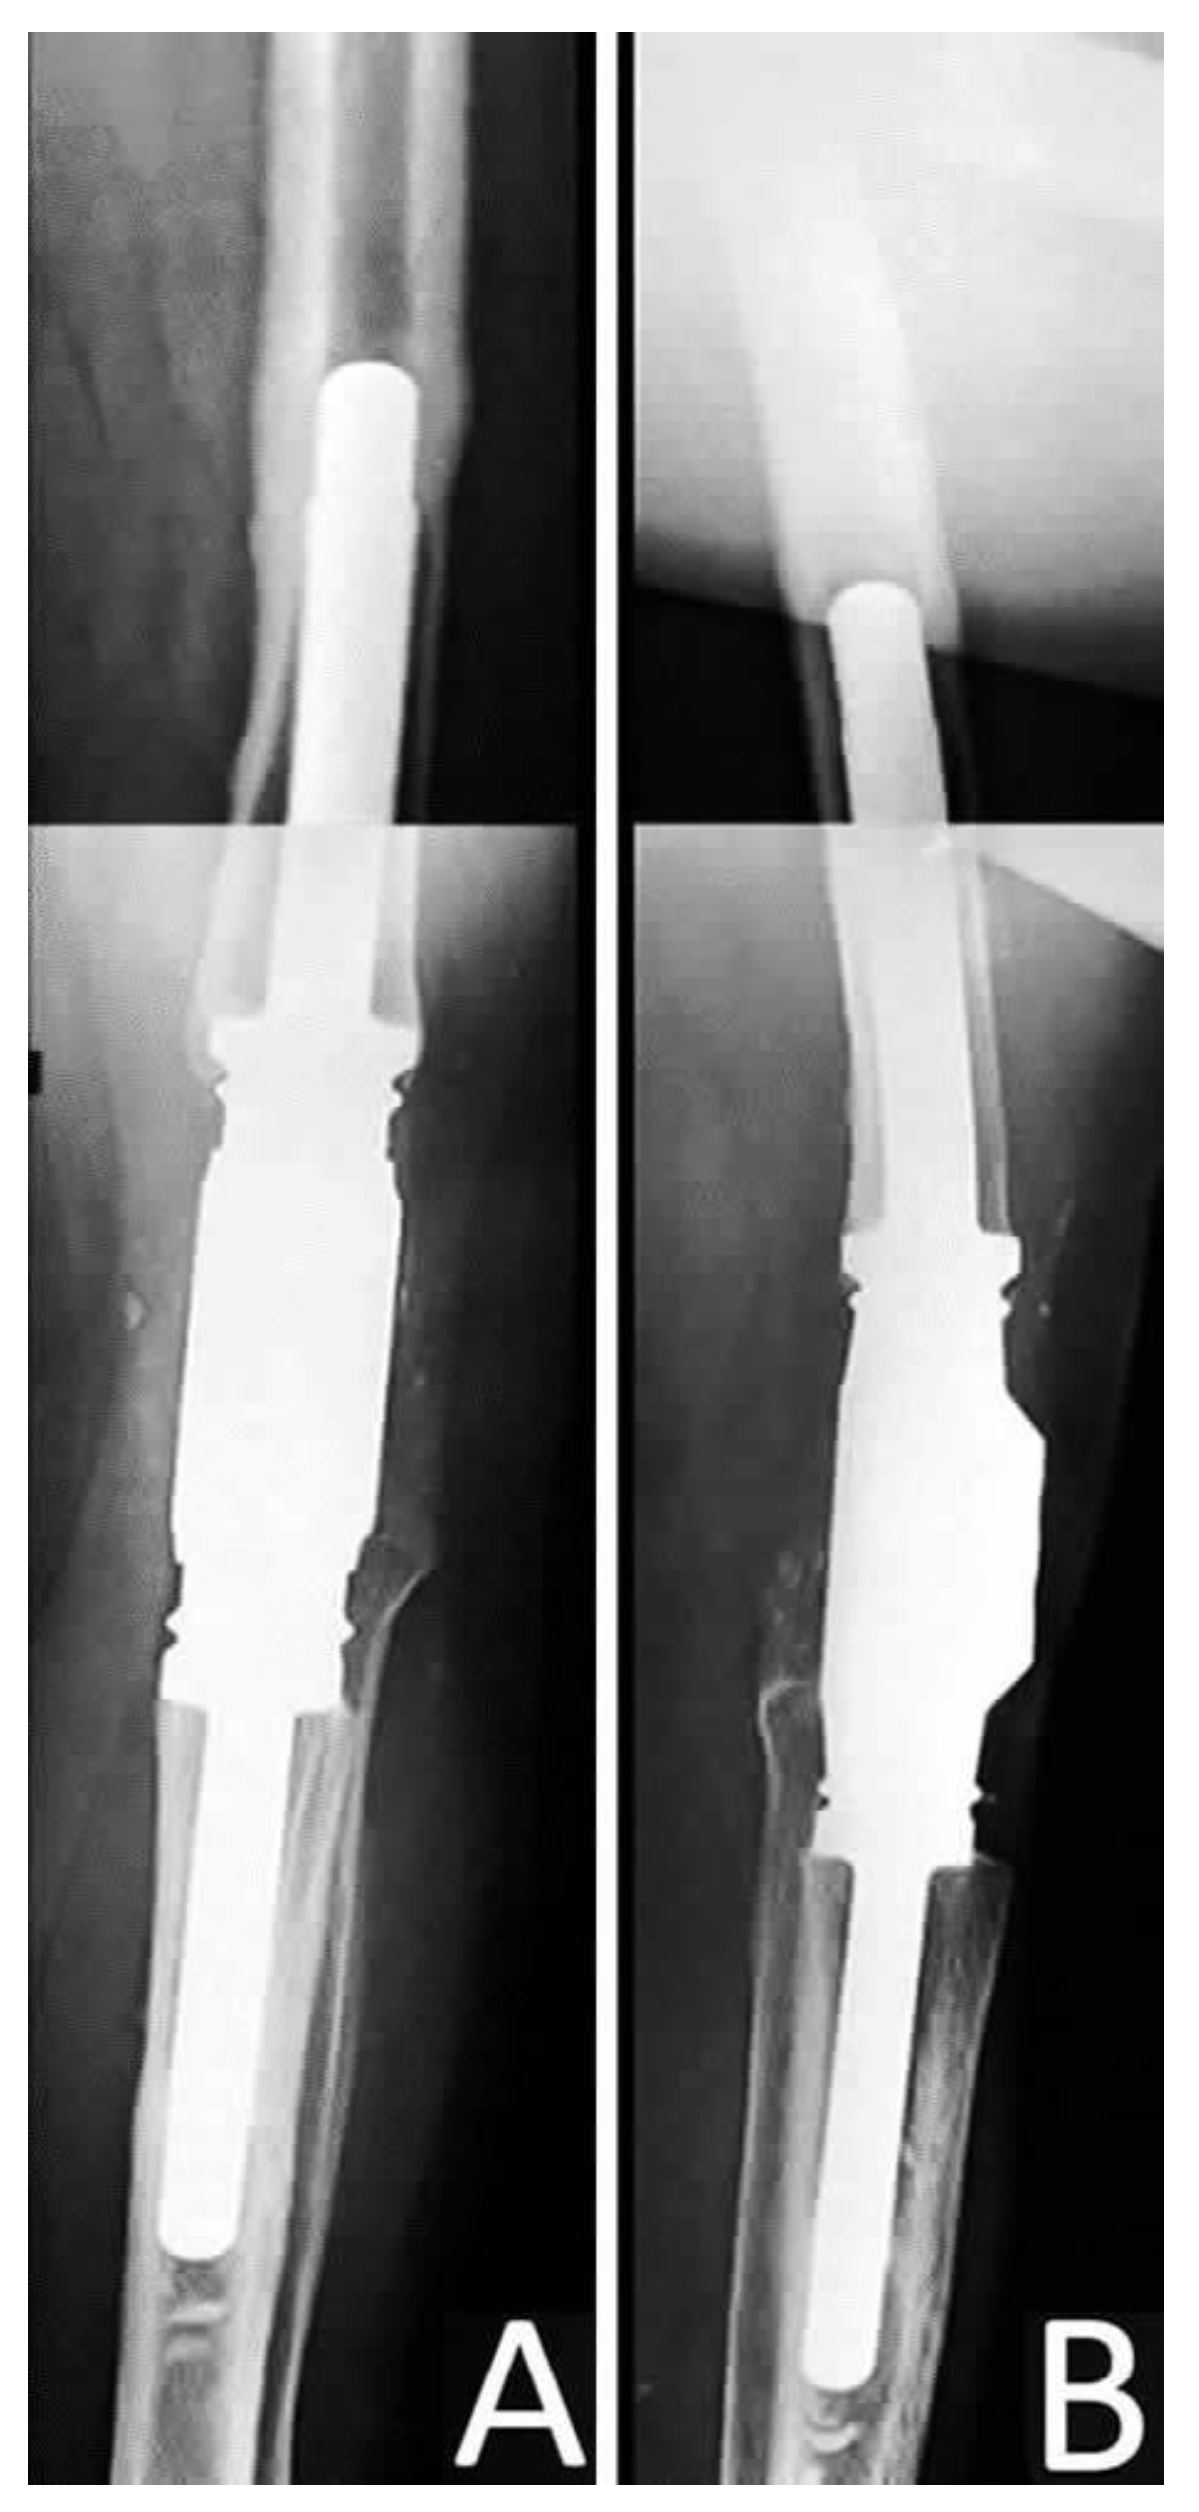

The primary endpoint was the outcome (success vs. failure) of the surgical treatment according to prosthesis survivorship during the postoperative period (Figure 6). The secondary endpoint was the assessment of the functional clinical results of the patients at their final follow up examination. The outcome was considered successful if no clinical or microbiological signs of infection were documented following surgical and antibiotic regime within the 24 months postoperative and patients achieved a painless, stable joint. Any other condition was considered as treatment failure [29]. The functional outcome was evaluated using the Visual Analogue Scale (VAS) for postoperative pain assessment and the Oxford Knee Score (OKS) [30,31]. All patients were ambulatory immediately at the first postoperative day with partial weight bearing, while full weight bearing began after 6 weeks.

Figure 6.

(A) Anteroposterior and (B) Lateral post-operative radiograph of the knee after the application of the silver-coated endoprosthesis.